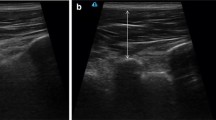

EMG signals were recorded from the left FDI muscle using Ag–AgCl surface electrodes placed over the belly and tendon of the FDI (see Fig. 1). The stimulation procedures were conducted using TMS. TMS was applied using a figure-of-eight coil (90 mm in diameter) that was connected to two Magstim 200 magnetic stimulators through a Bistim module (Magstim Company Limited, UK). The motor area corresponding to the left FDI muscle was located using the 10/20 International system for electrode placement (Trans Cranial Technologies 2012). The coil was positioned over the optimal location to produce a MEP in the contralateral FDI at a 45° angle from the inter-hemispheric line, with the handle pointing toward the right-hand side, to stimulate current flow in a posterior to anterior direction.